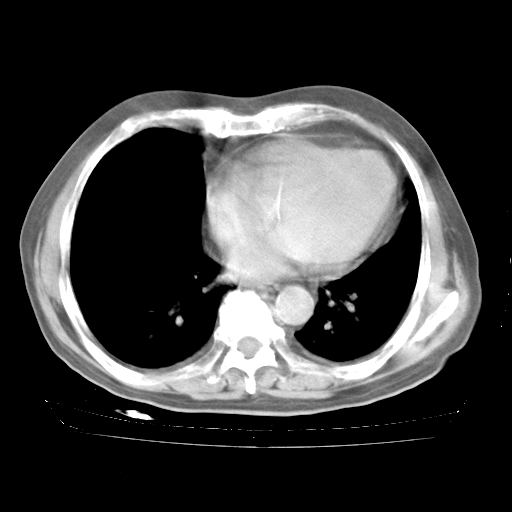

4月28日肺部CT——再次出现类似去年5月9日——透光度降低,“间质性”改变。

4月28日肺部CT——再次出现类似去年5月9日——磨玻璃样、间有“粟粒样”改变。

4月28日肺部CT